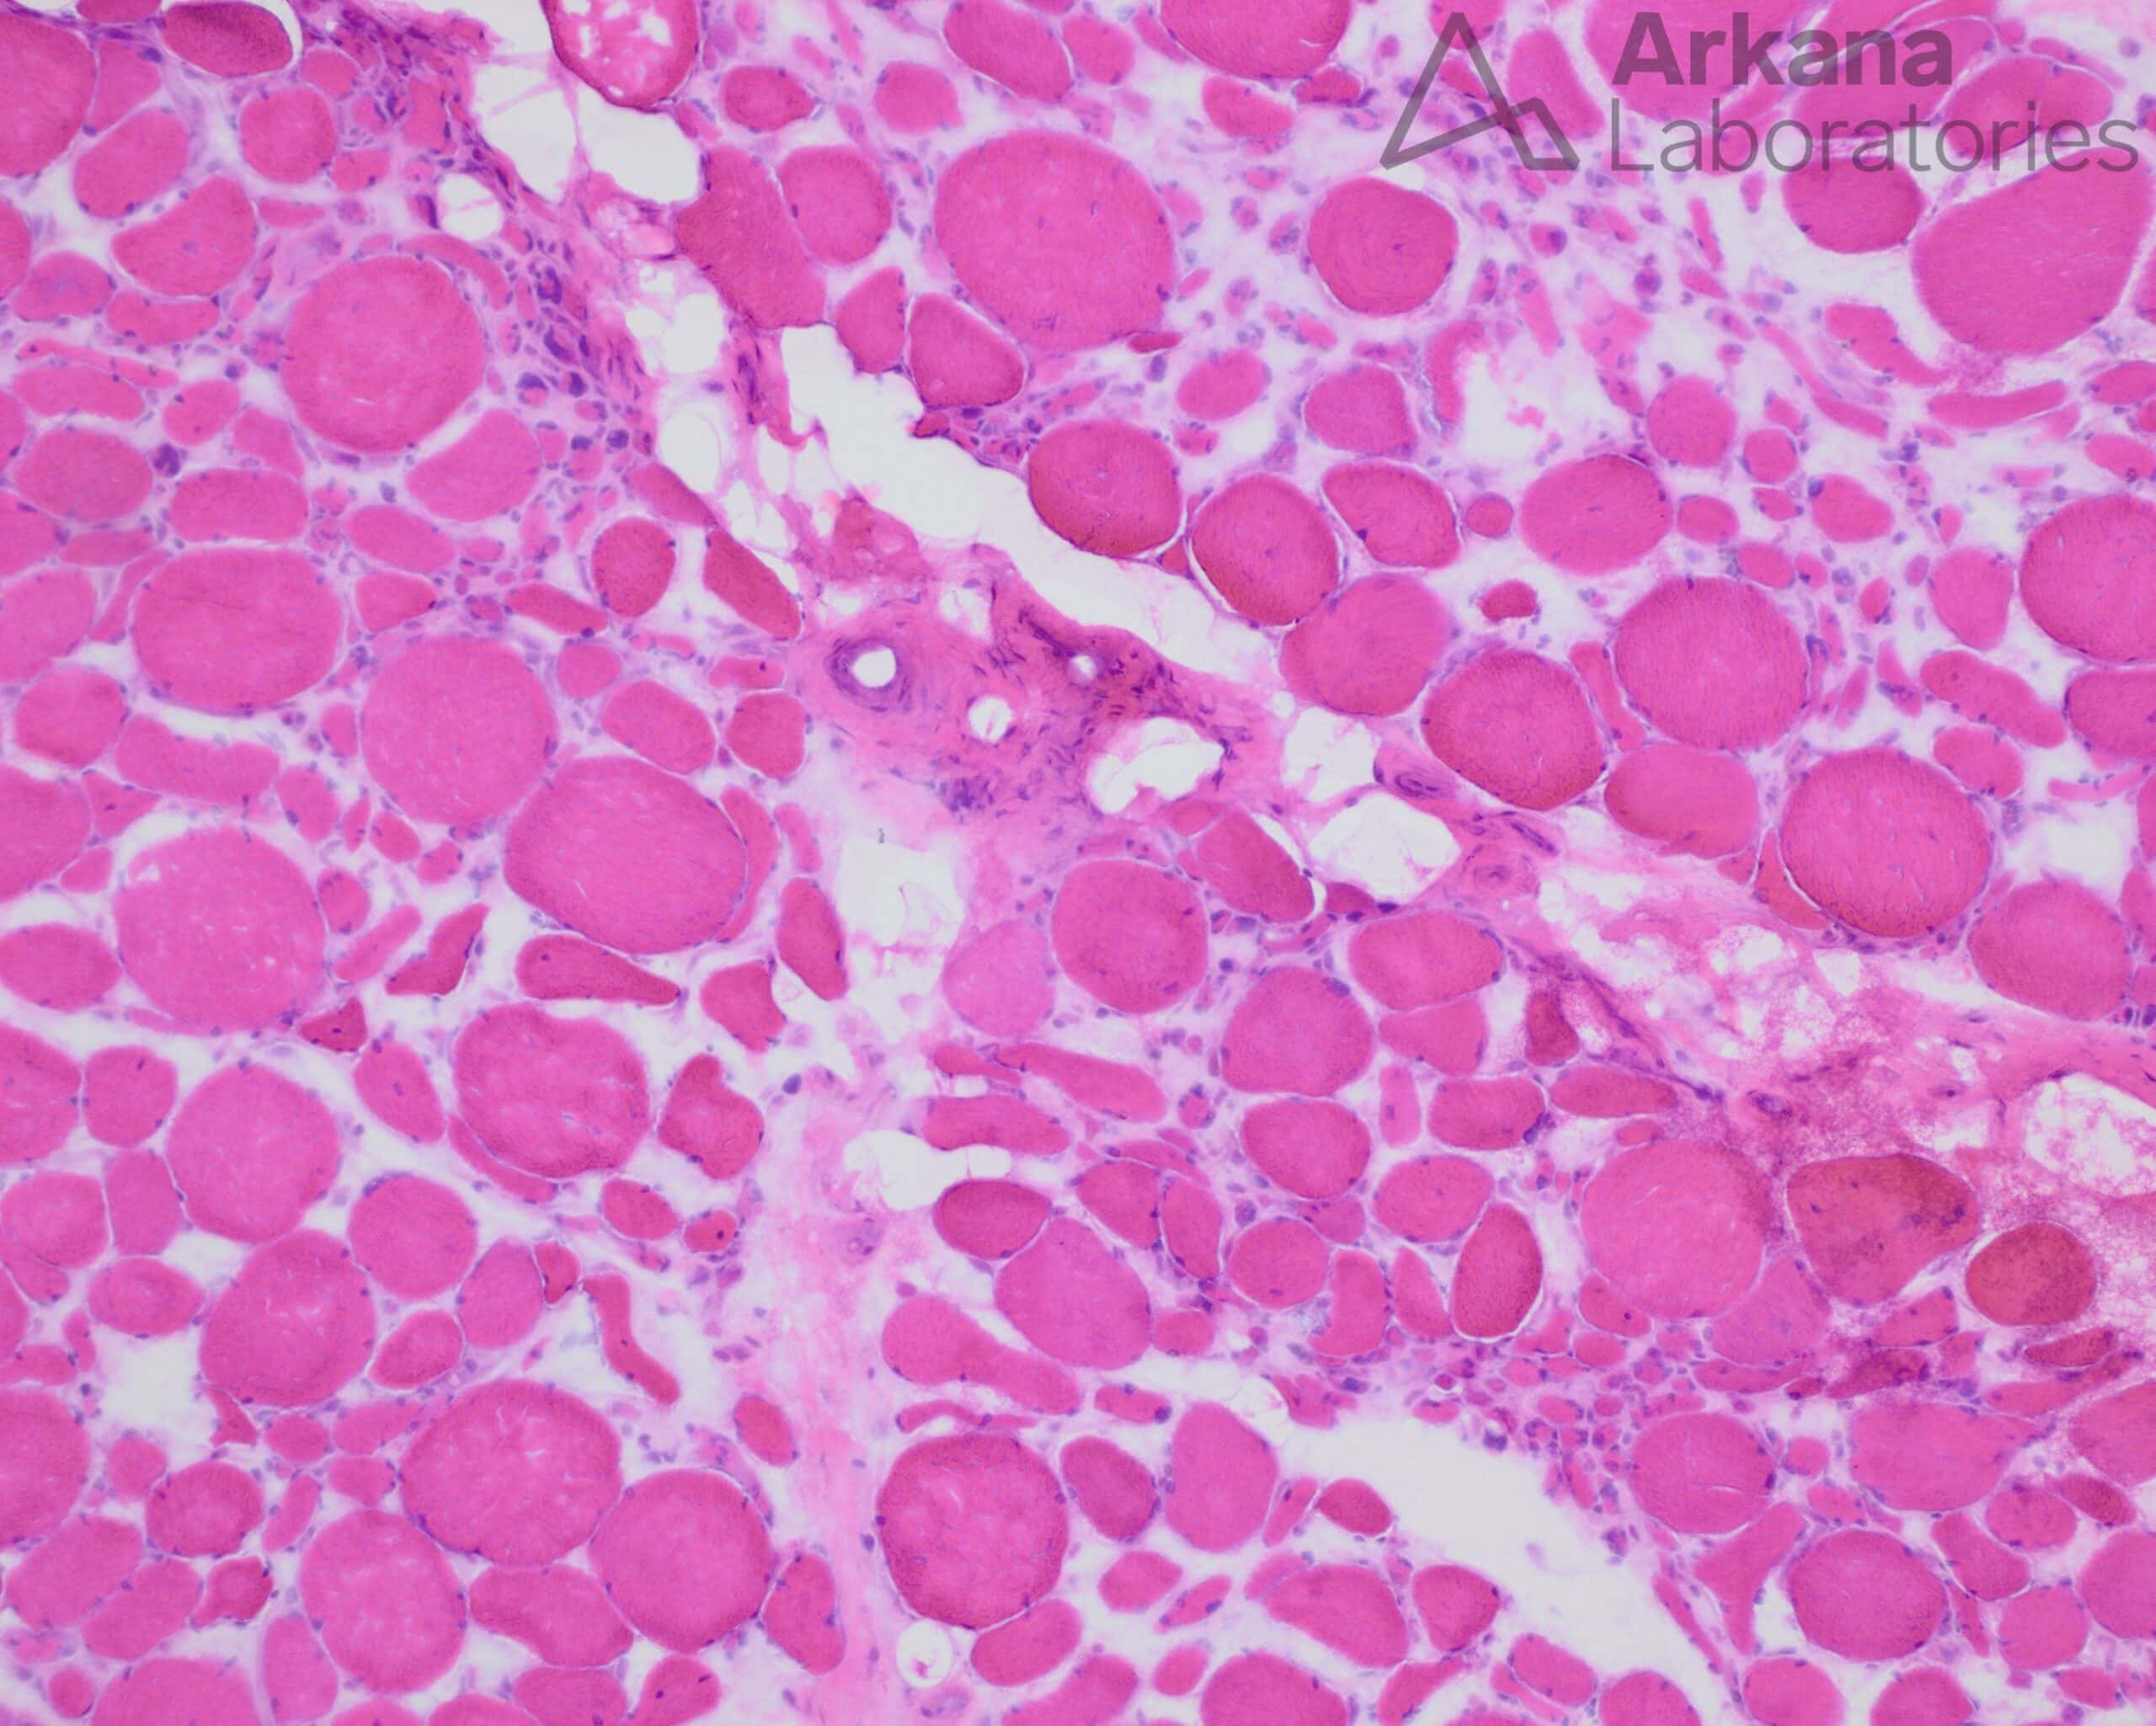

The findings in this muscle that are characteristic for active neurogenic changes are:

- Angulated atrophic fibers that stain darkly on esterase, along with nuclear bags.

- There is also a characteristic “Target” fiber with a light center surrounded by darker staining.

- The trichrome also reveals a peripheral nerve that appears partially depopulated of myelinated axons (red staining).

There is no necrosis, regeneration, fibrosis or internalized nuclei to suggest a myopathic process. Dystrophic muscle would show similar myopathic findings along with marked variation in fiber size and hypertrophic fibers with splitting. An inflammatory processes would most likely be characterized by the presence lymphocytes.